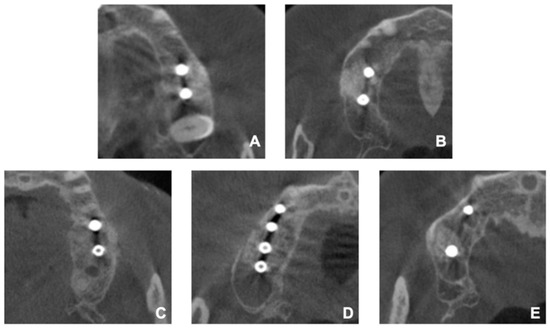

2. Materials and Methods

2.3. Fabrication of the Surgical Guide

2.4. Surgical Procedure